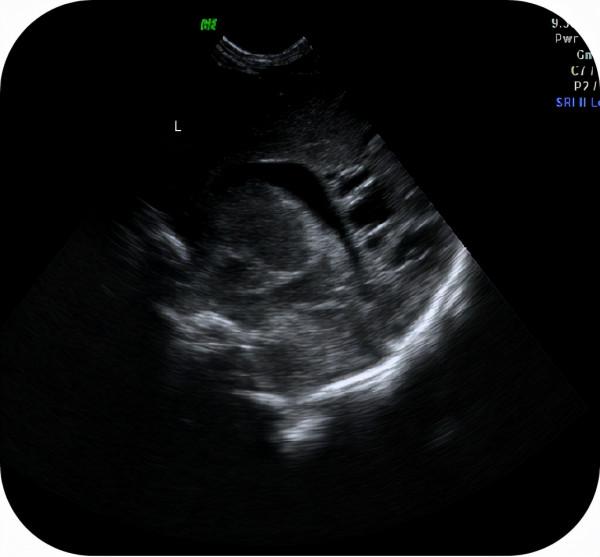

1.新生兒顱內出血;

顱內出血是指血管破裂從而引起出血,進而會造成腦缺氧。

在新生兒群體當中,發生顱內出血的機率十分高,因為新生兒的腦部發育不成熟,腦部血管管壁較薄,血管很容易破裂,懷孕期間出現妊娠期糖尿病或高血壓的產婦生下來的新生兒出現顱內出血的機率更大。